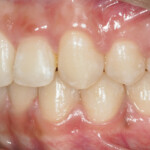

This is an example of a teenage patient with photographs of their smile before and after treatment at Braceline. Our orthodontic treatments are designed to provide maximum results in minimal time and to help you achieve the smile you always wanted!

After Transformation!